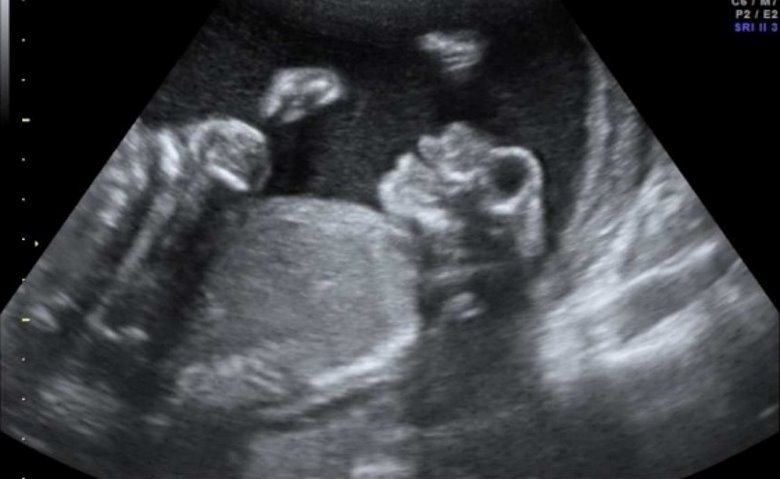

El caso que hoy nos ocupa es el extremo indudable de esta malformación, constituida por la ausencia de corteza cerebral y persistencia solo del tronco encefálico.

Los medios de comunicación de nuestra ciudad fueron conmovidos recientemente por una noticia dolorosa, una joven mujer de 24 años cursaba sus 16 semanas de embarazo de un feto anencefálico y víctima de un intenso shock por el diagnóstico, peticionaba, envuelta en su sufrimiento y su angustia, la interrupción del mismo.